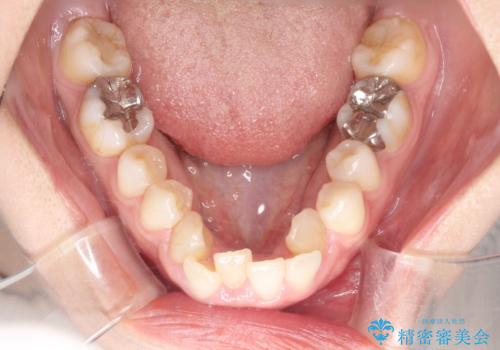

【ワイヤー矯正】前歯の凸凹を非抜歯で治療

- 前歯の凸凹を主訴に来院されました。

側方拡大にてスペースを作ることにより綺麗に前歯を並べることができました。

前歯の凸凹がある場合は治療計画を立てる上でスペースをどのように作るかが重要になります。

今回の場合は主に側方拡大でスペースの確保を行いました。